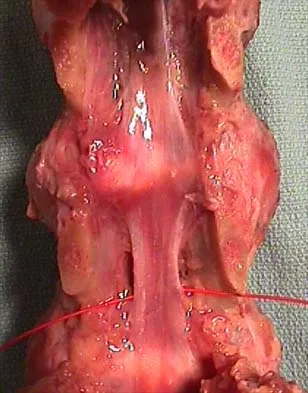

Figures 34a through 34c show an axial proton density (spin echo long TR, short TE) image, a sagittal inversion recovery (STIR) image, and a sagittal T1-weighted (short TR, short TE) image of the left thigh. What is the most likely diagnosis?

Explanation